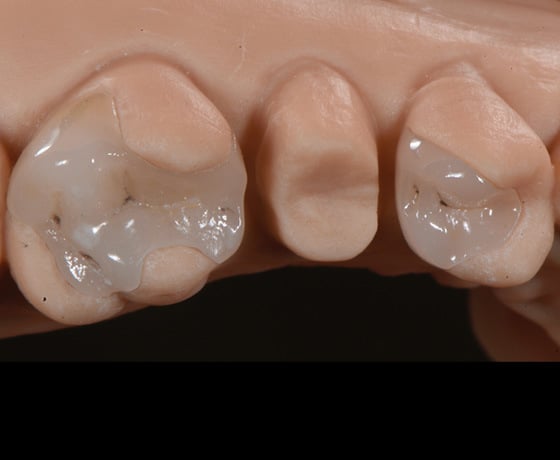

Situazione iniziale e isolamento del campo con diga di gomma.

Rimozione e pulizia delle carie del primo molare in amalgama e del primo premolare in composito.

CAD/CAM, restauri parziali in disilicato di litio in un modello stampato in 3D.